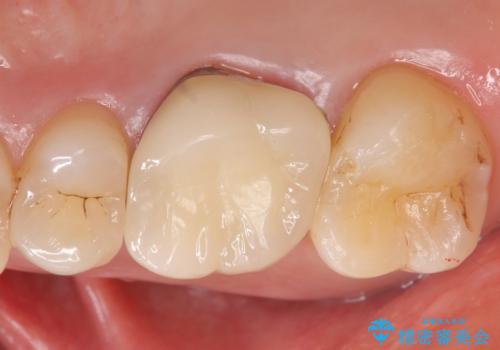

メタルボンドクラウン ゴールドから白い歯へ

- 見た目が気になるため右上6のゴールドクラウンをセラミックにしたいといらっしゃった方の症例です。

再根管治療を御希望されたため根管治療を行った後、メタルボンドクラウンによる補綴を行いました。

金属フレームを用いたメタルボンドクラウンは、オールセラミッククラウンに比べ審美性で劣るというイメージが強いです。しかし歯肉の下までしっかりと被せれば、唇・頬側からは金属部が見えず、十分に審美的です。

また適合もよく、強度も高いので、奥歯の補綴には適したクラウンです。